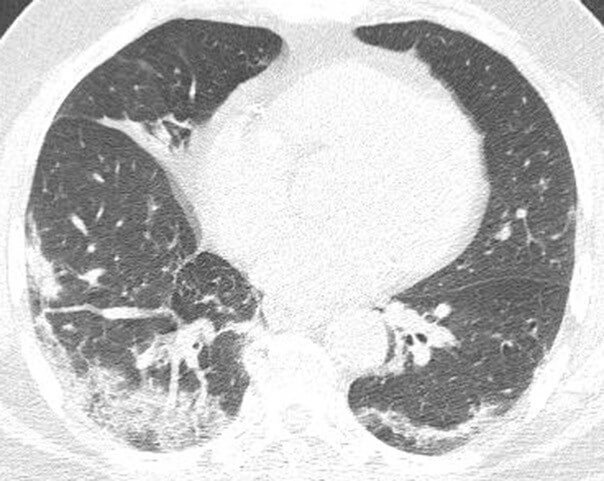

During the COVID-19 pandemic, radiologists continue to study chest radiographic and CT findings of patients with COVID-19 to determine patterns. Common imaging findings of nonbreakthrough (or typical) COVID-19 cases include bilateral consolidation and ground-glass opacity that may be peripheral or diffuse in distribution. According to Dr. Elicker, the imaging appearance suggests that organizing pneumonia is a relatively common pattern of injury in these patients as evidenced by the presence of perilobular opacities and/or the reversed halo sign in many patients. More severe manifestations include diffuse alveolar damage, which on imaging manifests as generalized ground-glass opacity and consolidation. “It is known that both diffuse alveolar damage and organizing pneumonia may, over time, result in lung fibrosis,” he says.

Findings from the University of Maryland study, led by Rydhwana Hossain, MD show that imaging findings in such patients are commonly mild and outcomes are generally favorable. The authors note that “larger studies are needed to establish imaging differences between breakthrough and unvaccinated populations.”